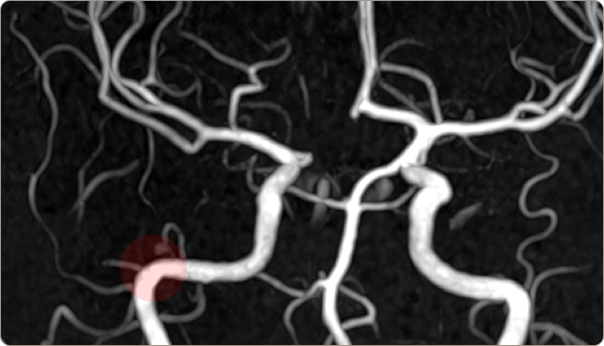

MRA

치매, 뇌종양, 뇌경색 등

뇌조직의 정밀 진단